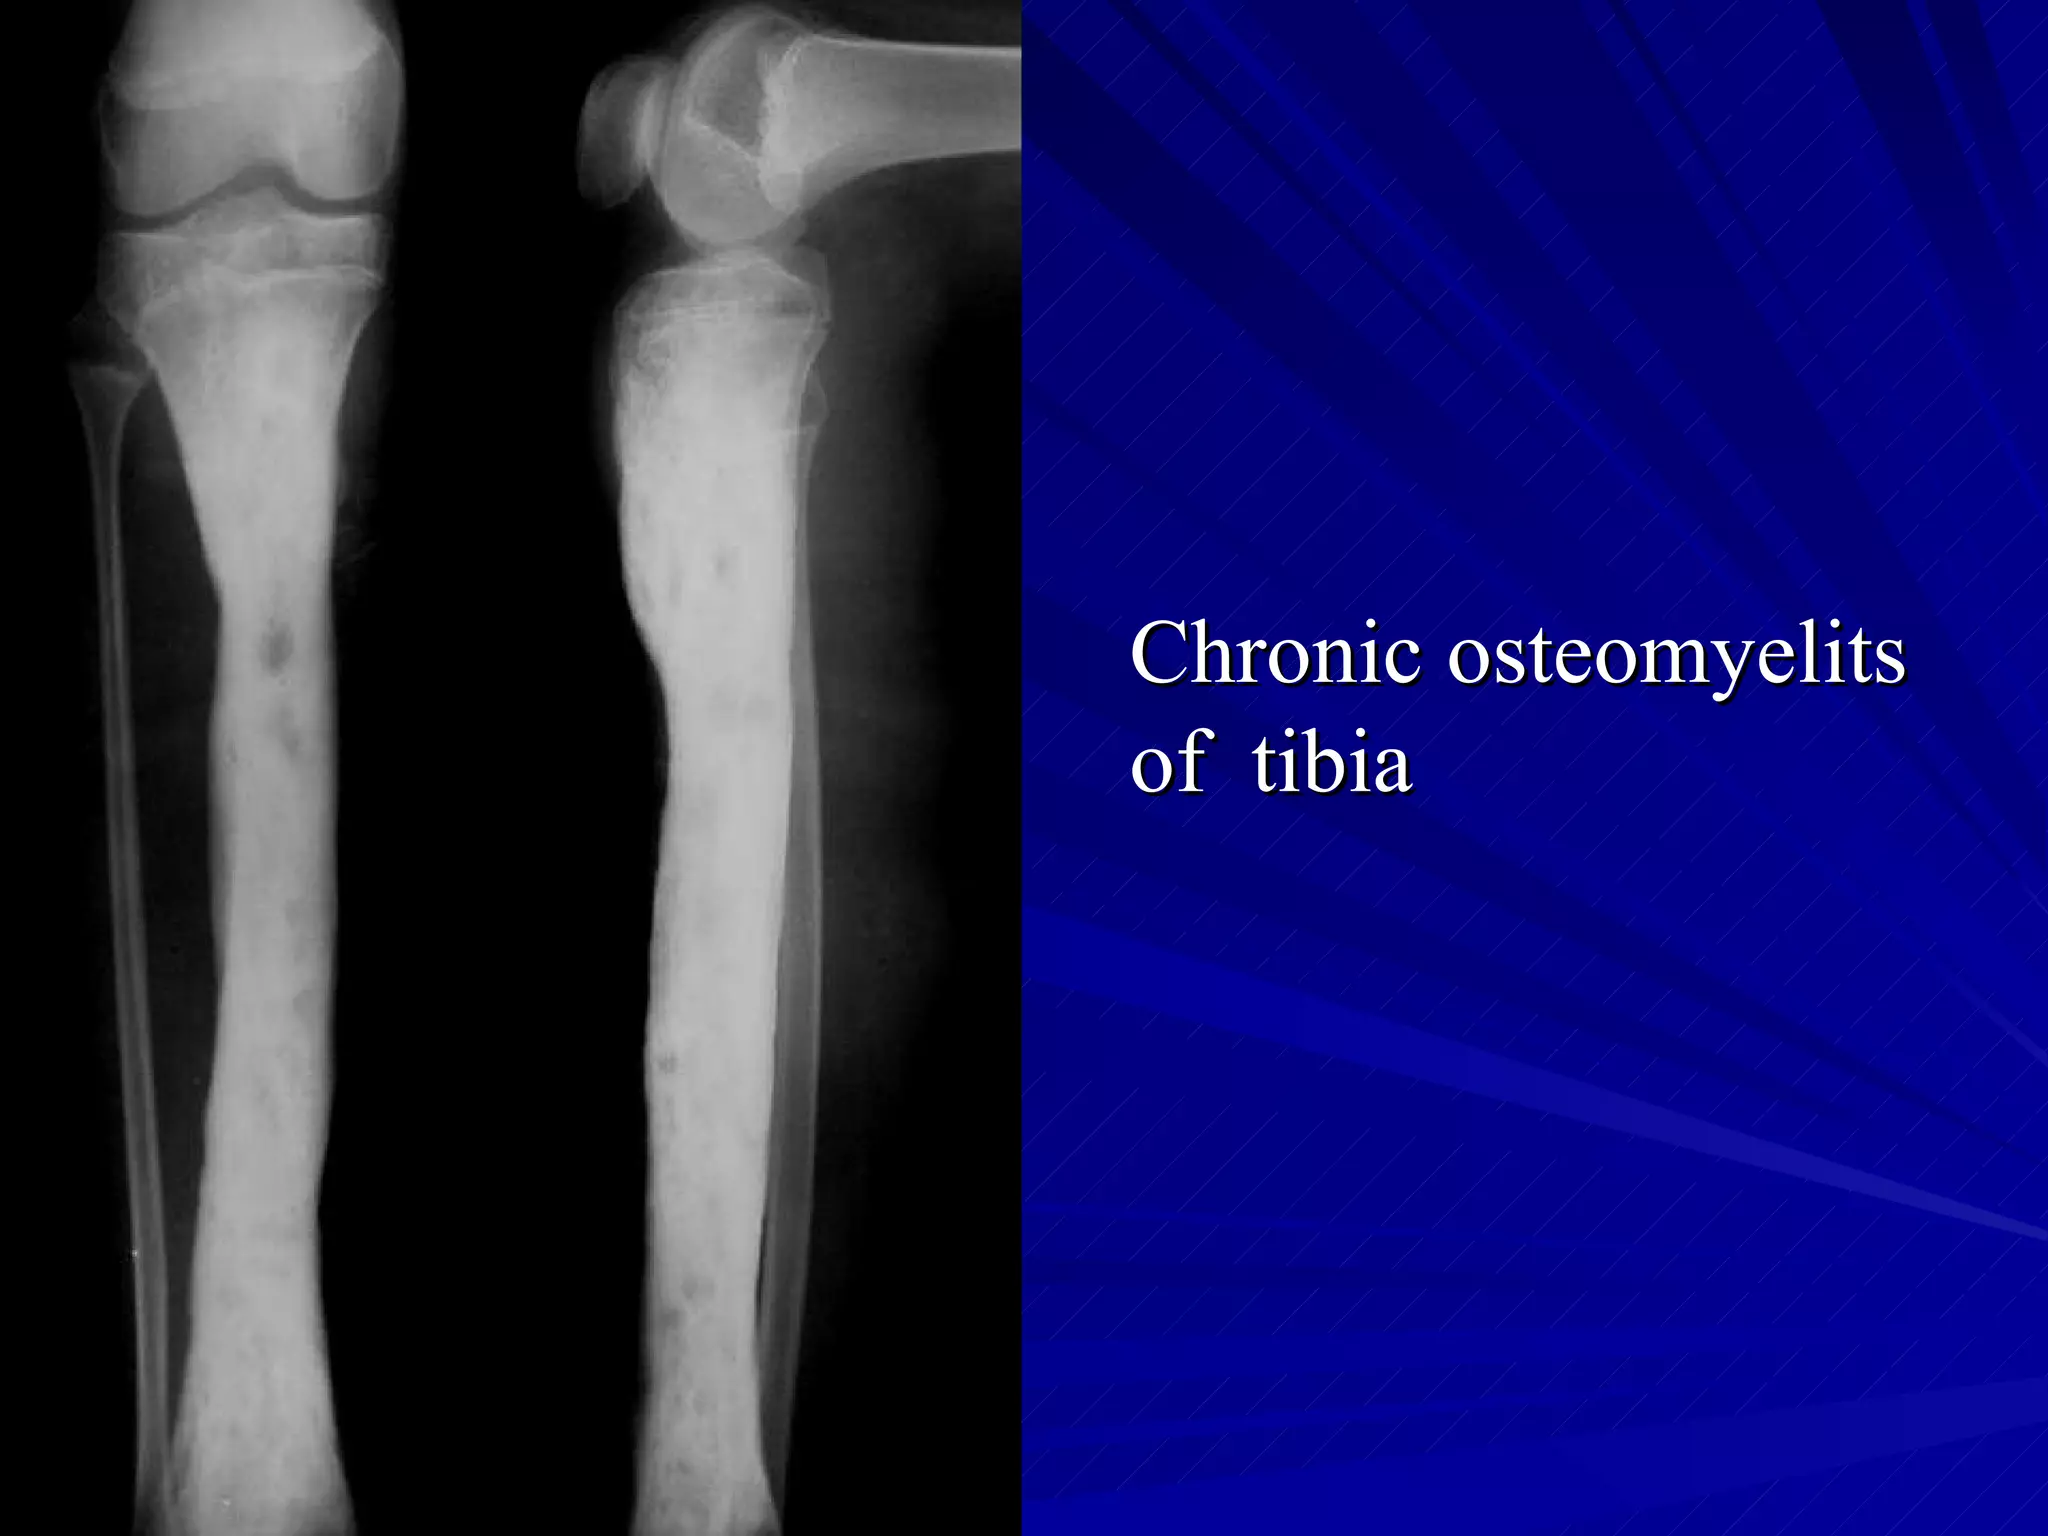

The document discusses various types of infectious diseases of bones and joints, including acute and chronic pyogenic osteomyelitis, Brodie's abscess, tuberculosis of long bones and the spine, and infectious arthritis. Specific examples provided include tuberculosis of the spine, hip, knee, and foot bones as well as pyogenic arthritis affecting the hip and knee joints. The document also mentions normal x-ray appearances of joints and basic features of joint diseases visible on x-rays such as swelling, destruction, degeneration, ankylosis, and dislocations.